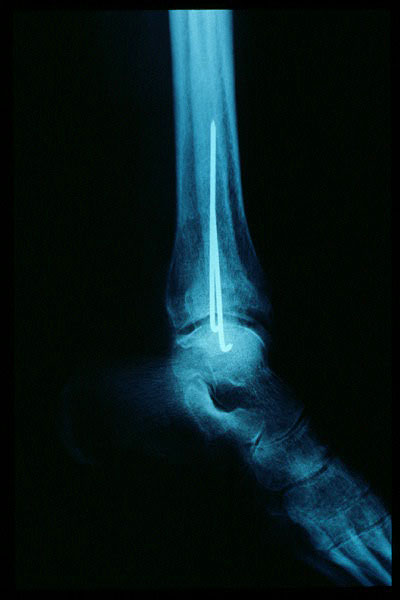

APR Fractura bimaleolar de tobillo

Fractura maleolo externo. Osteosíntesis.